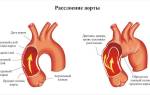

Когда речь заходит о клипировании аневризмы, подразумевается процедура, направленная на изоляцию аневризмы от общего кровообращения. Это достигается путем установки специальной клипсы на шейку пораженного сосуда.

Клипирование аневризмы сосудов — это хирургическая процедура, направленная на предотвращение разрыва аневризмы, что может привести к серьезным осложнениям, включая инсульт или смерть. Врачи отмечают, что данная операция позволяет создать барьер, который изолирует аневризму от кровотока, тем самым снижая риск ее разрыва. Однако, как и любая хирургическая манипуляция, клипирование может иметь последствия. Среди них — возможность повторного появления аневризмы, неврологические нарушения, а также инфекции. Врачи подчеркивают важность тщательной диагностики и индивидуального подхода к каждому пациенту, чтобы минимизировать риски и обеспечить наилучший исход. В целом, при правильном выполнении и соблюдении всех рекомендаций, клипирование аневризмы может значительно улучшить качество жизни пациента и продлить его жизнь.

Клипирование аневризмы сосудов — это хирургическая процедура, направленная на предотвращение разрыва аневризмы, которая представляет собой расширение стенки сосуда. Многие пациенты и их близкие выражают опасения по поводу последствий этой операции. Некоторые отмечают, что после вмешательства могут возникнуть головные боли, слабость или изменения в когнитивных функциях. Однако большинство людей сообщают о положительном опыте, отмечая, что клипирование помогло избежать более серьезных осложнений, таких как инсульт. Важно, чтобы пациенты обсуждали все возможные риски и преимущества с врачом, чтобы принять обоснованное решение. Поддержка со стороны семьи и друзей также играет ключевую роль в процессе восстановления.

Если отказаться от лечения, аневризма будет постепенно увеличиваться, что в конечном итоге может привести к ее разрыву и кровоизлиянию, что часто заканчивается летальным исходом.